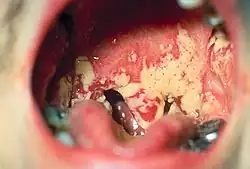

Pseudomembranous candidiasis of the posterior mouth and oropharynx

• Oral candidiasis is by far the most common fungal infection that occurs in the mouth. It usually occurs in immunocompromised individuals. Individuals who have undergone a transplant, HIV, cancer or use corticosteroids commonly develop candida of the mouth and oral cavity. Other risk factors are dentures and tongue piercing. The typical signs are a white patch that may be associated with burning, soreness, irritation or a white cheesy-like appearance. Once the diagnosis is made, candida can be treated with a variety of anti fungal drugs.[26]